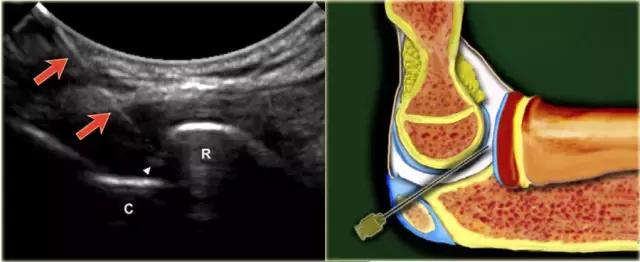

针对肘的注射,患者仰卧,臂在90°弯曲,升高并搁置在垫子上。桡骨小头与肱骨小头之间的关节间隙很容易触及。 手必须是旋前或可以变成拇指向上的位置,以最大程度地打开关节。

探头被放置在关节可视关节间隙。针(22号,30mm)在关节的背外侧朝向朝向桡骨头的关节表面的关节空间以微小的头尾向角指向。

当看到已经进入关节并且感觉到径向头部的软骨时,针被稍微拉回,以确保斜面从离开软骨并且面向关节。注射5-8mL的造影剂。 不应感觉到注射阻力。